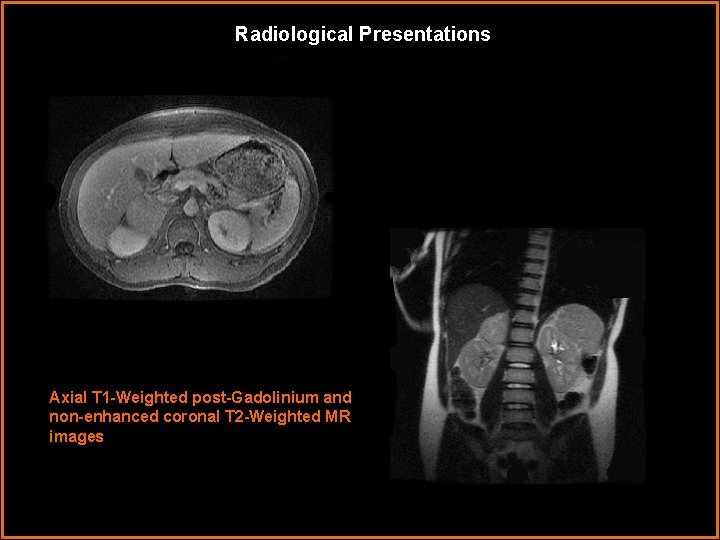

Radiological Presentations Axial T 1 -Weighted post-Gadolinium and non-enhanced coronal T 2 -Weighted MR images

Findings and Differentials Findings: Ultrasound images demonstrate a solid 6 cm mass superior to the right kidney. The transverse image shows the mass in close approximation to the liver and gall bladder with internal vascularity. MR imaging confirms that the mass arises from the right adrenal gland. Early contrast enhancement is demonstrated on the T 1 W sequence. The tumor is slightly hyperintense on the T 2 -weighted image. Of note, the left adrenal gland is unremarkable. Nuclear medicine octreotide imaging demonstrates increased uptake in the right adrenal mass suggesting somatostatin receptors and a neuroendocrine origin. Differentials: • Pheochromocytoma • Adrenal Adenoma • Adrenal Cortical Carcinoma